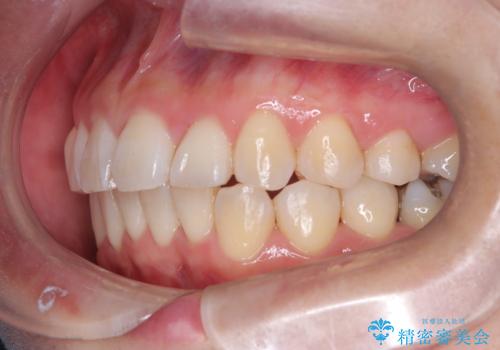

- 「歯のガタつきが気になる」「前歯の真ん中がずれている」との主訴で来院されました。診察の結果、上下の歯列に中等度の叢生(凸凹)があり、特に前歯の位置のずれ(正中の偏位)が目立つ状態でした。見た目だけでなく、かみ合わせにも影響を与える可能性があるため、全体的なバランスの改善が必要と診断しました。

治療はインビザラインを使用し、1~2週間ごとに新しいマウスピースに交換しながら段階的に歯を移動させていきました。特に上下の正中が揃うよう、奥歯や前歯の位置関係に注意を払いながら細かく設計を調整。途中の確認でも、左右のバランスが取れてきたことをご本人も実感されていました。

治療期間は約1年半で、ガタついていた歯列はきれいに整い、上下の前歯の真ん中もぴったりと揃えることができました。透明なマウスピースのため周囲に気づかれず治療が進み、快適に続けられたとの感想もいただいています。